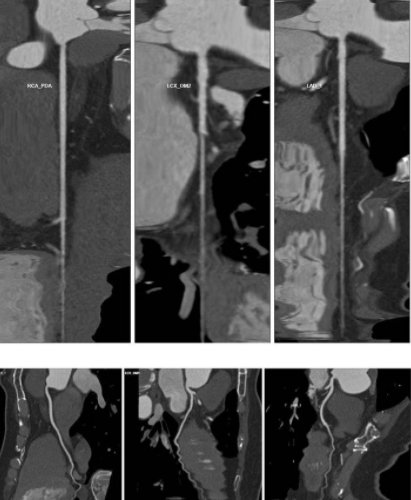

其中,冠状动脉CTA是一项无创性血管检查技术,该技术在冠心病的筛查、术前病情评估、冠脉变异和畸形的评价、心功能分析等方面发挥着重要作用,冠状动脉CTA检查已成为排除冠心病的重要手段,成功率在95%以上。冠状动脉CTA不但“无创”,而且其检查费用要比常规冠状动脉造影低得多,CT检查流程于门诊即可完成,无需住院。

冠状动脉CTA可以用于诊断冠心病、冠状动脉粥样硬化板块及管腔狭窄程度分析、血管走行分析(浅肌桥-壁冠状动脉分析);心脏肿瘤诊断、粘液瘤、室壁瘤、瓣膜疾病、房缺、室缺等室血管病变。